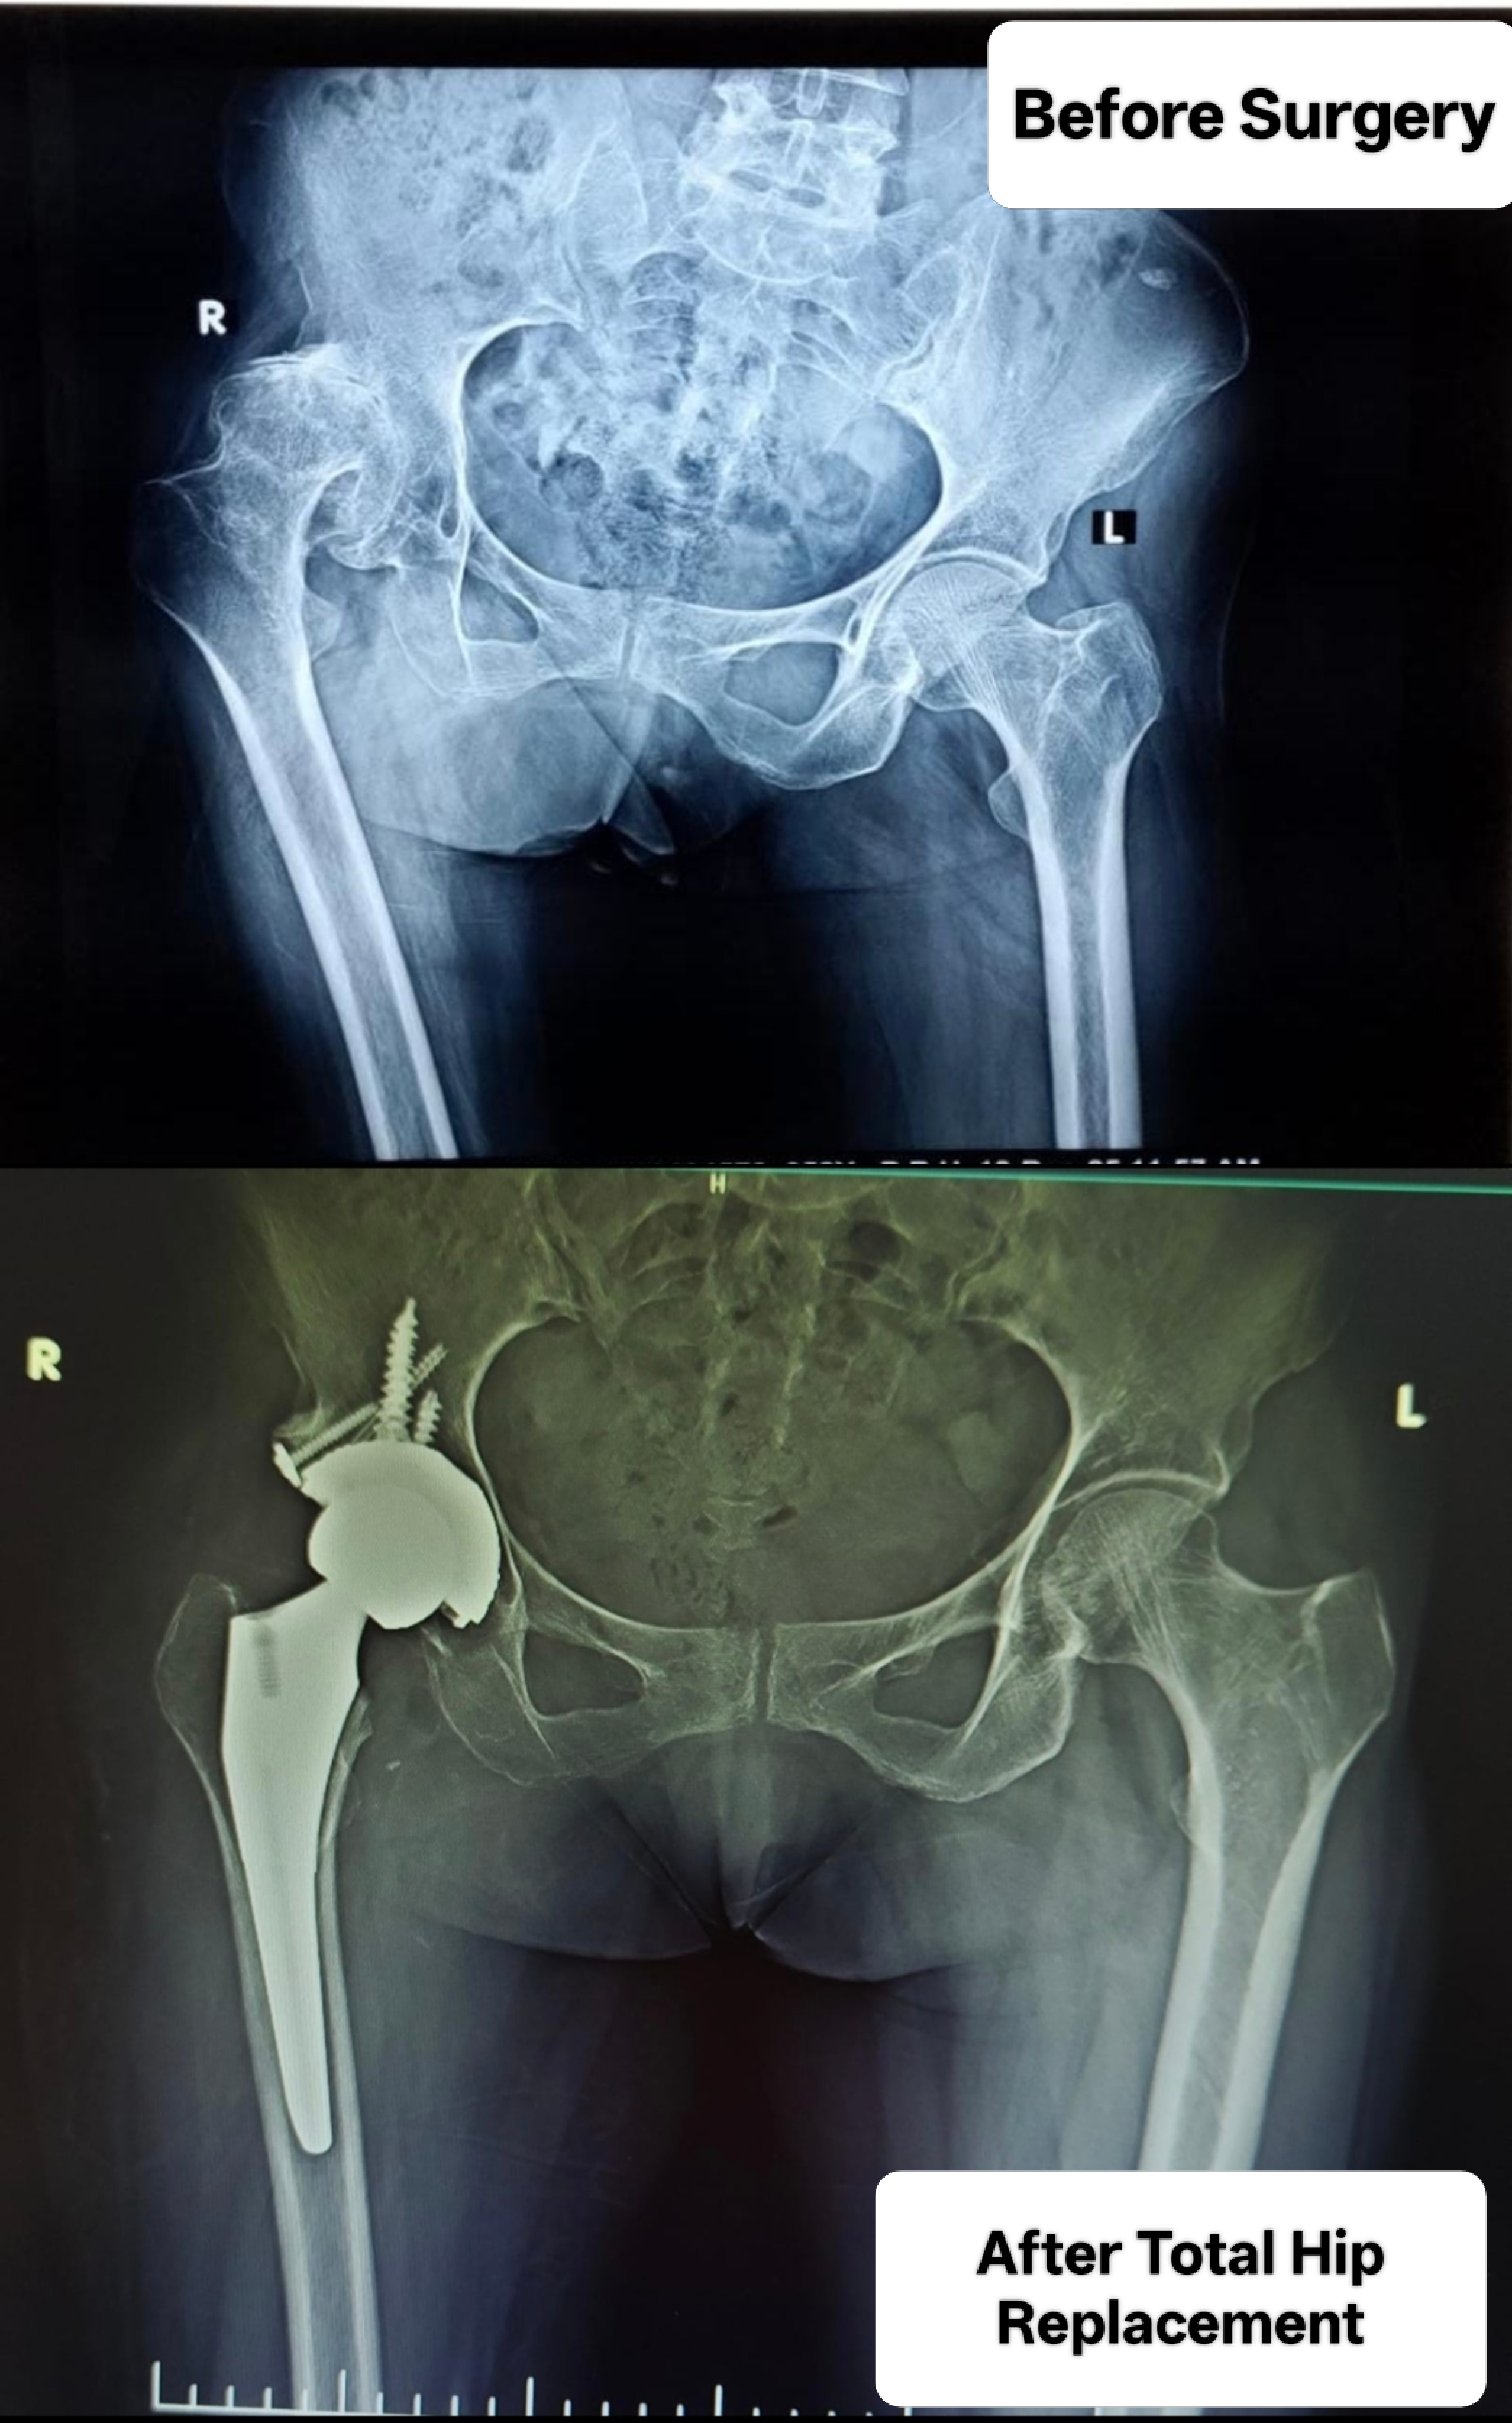

Welcome to the world of orthopedic excellence, where your health and well-being are our utmost priorities. Dr. Chetan Singh , an accomplished orthopedic surgeon, has been a dedicated practitioner in the vibrant city of Bhopal for the past 8 years. His unwavering commitment to providing exceptional orthopedic care has earned him a reputation as a trusted healthcare professional in the region. Meet Dr. Chetan Singh is a highly skilled orthopedic surgeon who has dedicated his career to improving the lives of patients suffering from orthopedic conditions. His educational journey began with the completion of an MBBS degree from Devi Ahilya Vishwa Vidyalaya, Indore, M.P. in 2015, where he laid the strong foundation for his medical expertise. Driven by his passion for orthopedics and a desire to offer the best care possible, Dr.Chetan Singh continued his educational journey. In 2019, he successfully achieved a Master of Surgery (MS) in Orthopedics from Madhya Pradesh Medical Science University, Jabalpur. This rigorous training equipped him with the knowledge, skills, and advanced techniques necessary to diagnose, treat, and manage a wide spectrum of orthopedic conditions.